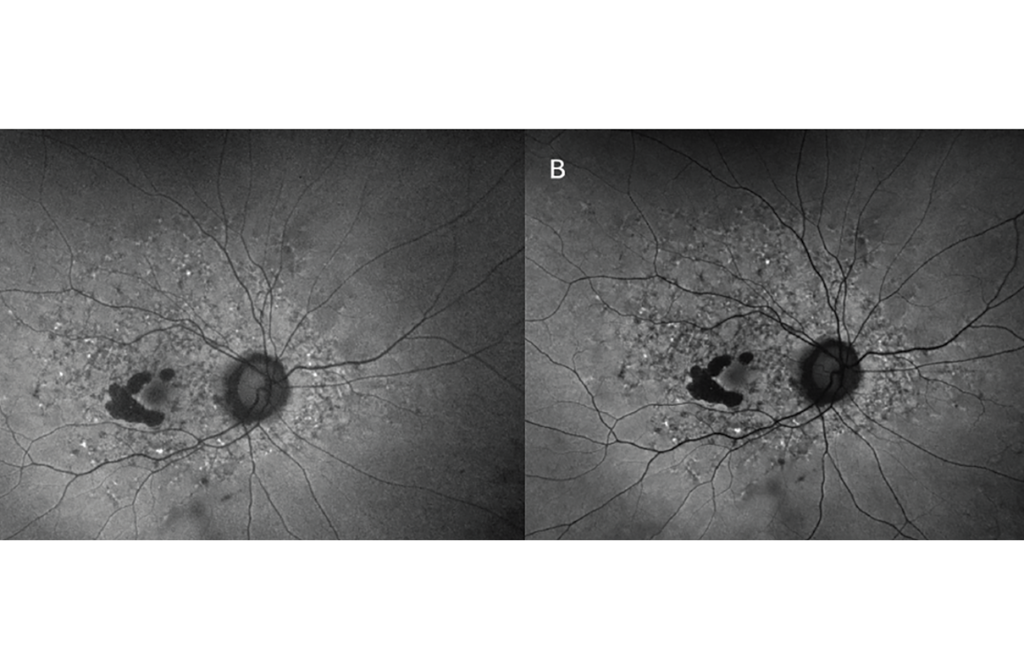

FIGURA 5

Existen innumerables aplicaciones de la FAF en la práctica clínica, siendo la más práctica detectar o monitorear la progresión de la AG en pacientes con DMAE. El Informe 3 de la Reunión sobre Clasificación de Atrofia (CAM) describió los hallazgos de la FAF en la AG como (1) bordes claramente demarcados, (2) una señal de hipo-AF similar a la cabeza del nervio óptico o los vasos sanguíneos de la retina, y (3) un diámetro de ≥250 µm. 10 La detección temprana de la AG es importante para la educación del paciente sobre su estado de enfermedad, así como para una posible intervención terapéutica. Alternativamente, la FAF se recomendó en las pautas de la Academia Estadounidense de Oftalmología de 2016 para la detección de la maculopatía por hidroxicloroquina y se recomienda anualmente además de la OCT y la prueba del campo visual 10-2 después de cinco años de uso del fármaco. 11 La FAF de campo ultra amplio también es una herramienta poderosa para detectar la enfermedad retiniana hereditaria o la enfermedad uveítica, las cuales a menudo tienen hallazgos tempranos sutiles en el examen clínico ( Figura 5 ).